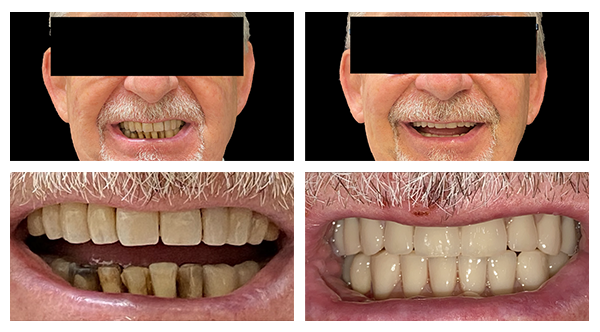

Caso Clinico Parodontite avanzata

DIAGNOSI

Caso di un paziente con diagnosi di parodontite avanzata con mobilità di tutti i denti.

TRATTAMENTO

bonifica dell'arcata superiore e inferiore e inserimento di 12 impianti con relativa protesi a carico immediato provvisoria, dopo i quattro mesi il paziente è ritornato per un esame radiologico (ortopantomografia) e la relativa impronta per la protesi definitiva

La professionalità degli interventi è la garanzia di risultati duraturi